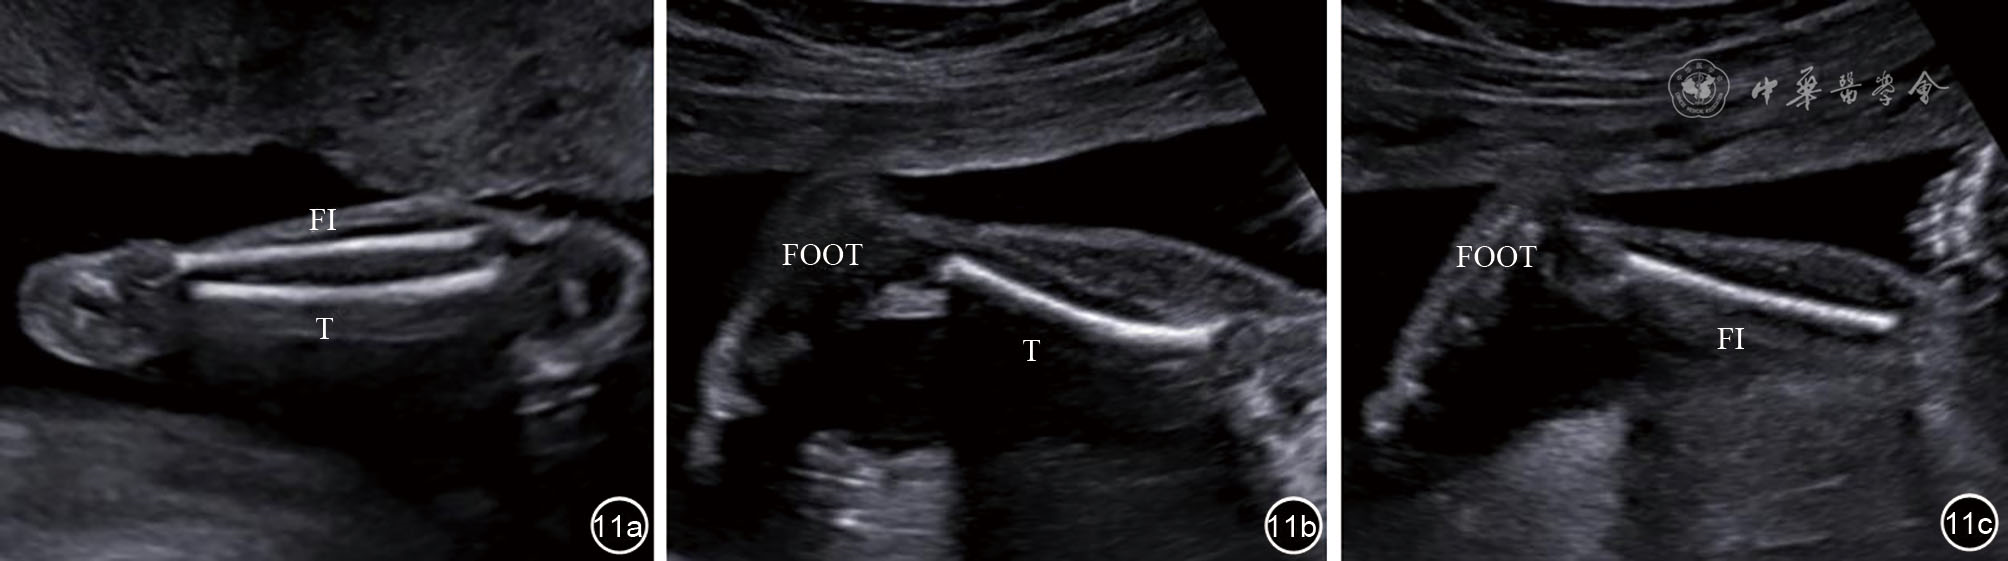

图11 胫、腓骨长轴切面超声图像。图a为胫、腓骨冠状切面;图b为胫骨矢状切面;图c为腓骨矢状切面 注:FI为腓骨;T为胫骨;FOOT为足